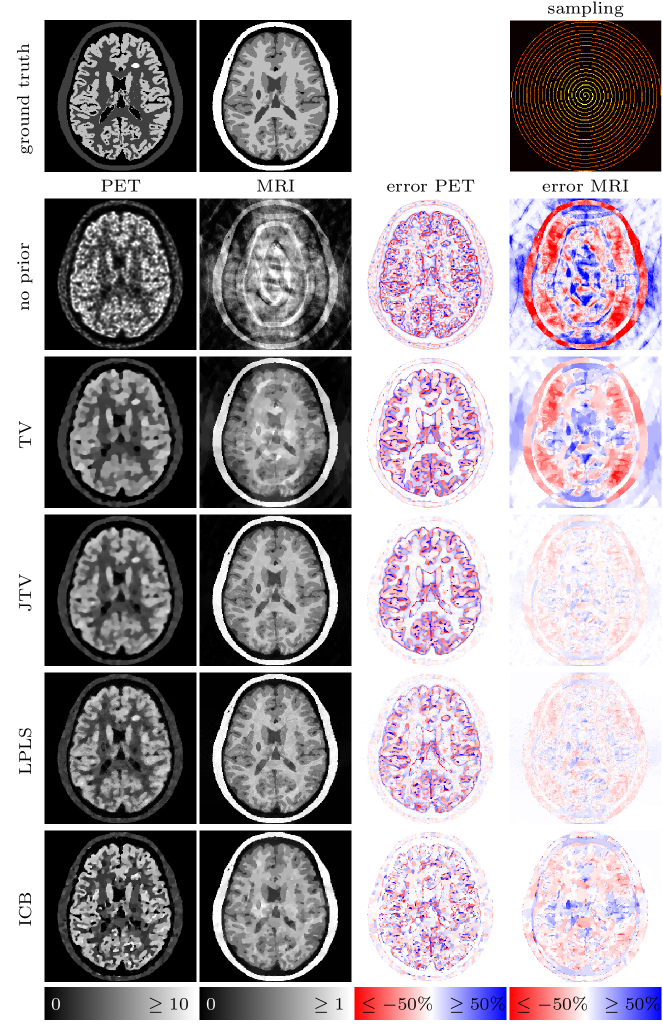

In case of MRI we use undersampled -space data, meaning that we sample the Fourier space only at a few frequencies specified by different geometries. For the sake of simplicity, the MRI operator hence consists of a 2-dimensional Fourier transform followed by a projection onto the geometric pattern of the corresponding sampling (cf. [20] . Note that we do not use a non-uniform Fourier transform since the chosen frequencies are still located on a Cartesian grid. However, the idea and method do not change for non-Cartesian methods. Eventually, Gaussian noise with an energy of approximately five percent of the total energy of the data set is added. We show four different types of undersampling in this work, which can be seen in Figure 6. The samplings introduce different types of artifacts and hence serve different purposes for the joint reconstruction setting which we elaborate on alongside with the results below.

![]() |

| (a) Full: | (b) Half: | (c) Spokes: | (d) Spiral: |

4.4 Results

Figures 9 to 12 show the results for four different MRI samplings and different types of regularization. The left two columns display the PET and MRI reconstructions, where all pictures are put onto the original scale of the ground truth, i.e. for PET and for MRI. If the reconstructions overestimate the image values beyond that scale, the corresponding pixels are set to the maximum value (note that an underestimation below zero is impossible due to the positivity constraint). The effective over- or underestimation of image values with respect to the ground truth can be assessed from the difference images on the right-hand side of the figures. Note that due to the missing weighting between gradients for JTV and LPLS, we had to rescale the PET data by a factor of in order to approximately provide the same range of image intensities for both PET and MRI. The results have then eventually been rescaled to their original range. We mention that due to the nonlinearity of the methods this may result in a slight change of quantitative values.

4.4.1 Full sampling

For a full sampling, already a separate reconstruction provides a visually perfect MR image, which remains the case for all priors. Here, the weighting for ICB is chosen such that the PET image does not influence the reconstruction of the MR image () and the procedure is similar to a PET reconstruction with an (evolving) anatomical prior. The MR reconstruction performed in parallel hence corresponds to a single channel BTV reconstruction. The quality of the PET image varies greatly. Without any prior, the PET image shows the typical noisy and blurry appearance of reconstructions from noisy Poisson data. The TV prior removes the noise, but highly oversmoothes the image. The first joint reconstruction method, JTV, is able to transfer some part of the sharp structures of the MR image to the PET image and increases its quality. However, the result remains too smooth. LPLS and ICB both show a substantial improvement of the image quality in terms of sharp edges and noise reduction. However, LPLS still features some remaining noise, and the lesion in the MRI not present in PET has been partly transferred. The result for ICB seems visually perfect on the shared structures of the image which can as well be assessed from the difference image. The only drawback is the smoothing of the hot lesion only present in the PET image, while we however observe that the MRI lesion has not been transferred. The observations are as well confirmed by the SSIM values in Table 1.

4.4.2 Half sampling

Sampling every second line of the k-space introduces a ghosting artifact into the MR image. JTV and LPLS show a similar performance in removing some parts of these artifacts from the MRI, while LPLS as well shows a clear improvement of the PET image. However, both lesions are again artificially shared between the images. The ICB results contain the least artifacts for MRI and the highest improvement for the PET image, where however again the hot lesion is attenuated. We as well find a slight transfer of the lesion from the MR image into the PET image, whereas the lesion from PET is not transferred to the MR image.

4.4.3 Spokes sampling

The situation for a spokes sampling is almost identical to a full MR sampling. Since already a TV prior removes the resulting grain artifacts, we again choose the weighting for ICB such that the PET image does not influence the MR image (). Interestingly, JTV and LPLS decrease the quality of the MR image, both visually and in terms of SSIM, by re-introducing some part of the noise. However, the PET image still benefits significantly from the influence of the MRI. ICB again shows the best performance for PET, sharpening the edges and restoring the quantitative values, where we again observe the attenuation of the hot lesion and transfer of the MR lesion.

4.4.4 Spiral sampling

For a spiral sampling, we again expect a mutual benefit for both modalities, since the sampling introduces some circular artifacts. Surprisingly, JTV delivers the best result in terms of SSIM, which however look too smooth. Visually the results for LPLS convince the most, both for PET and MRI. The ICB result for PET is sharper and more accurate in terms of quantitative values, but appears a little too noisy, which can as well be caused by the influence of the undersampled MR image.